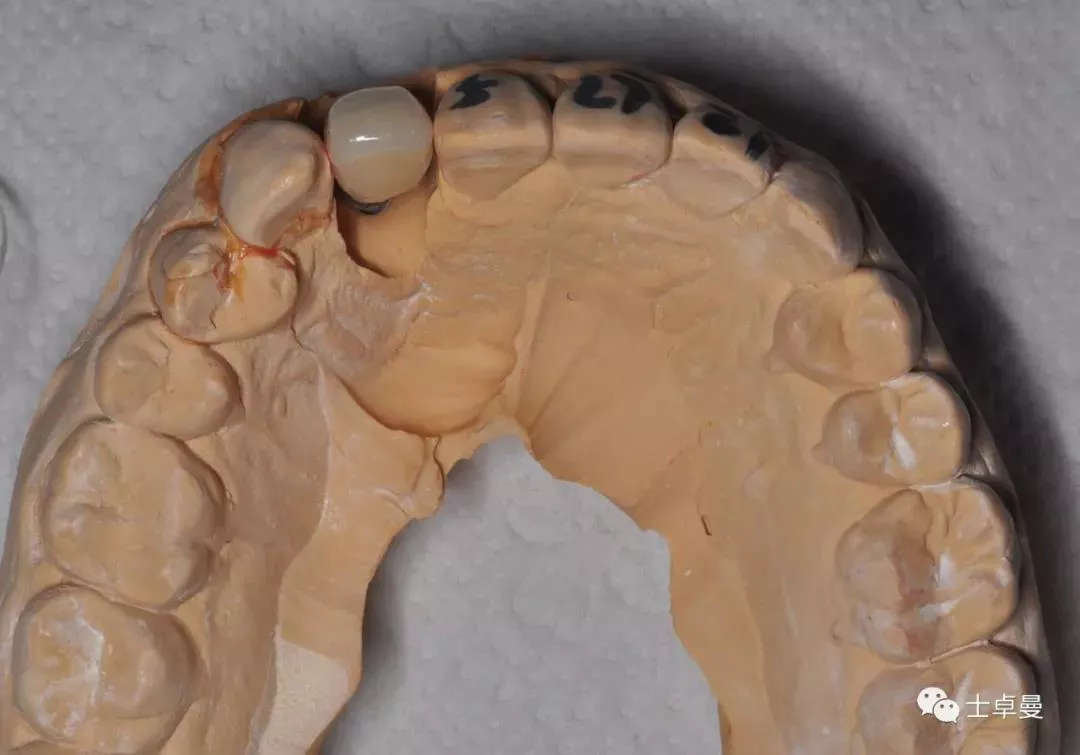

临时义齿完成

·       临时义齿戴入正中,前伸侧方均无咬合接触;

临时义齿口内就位